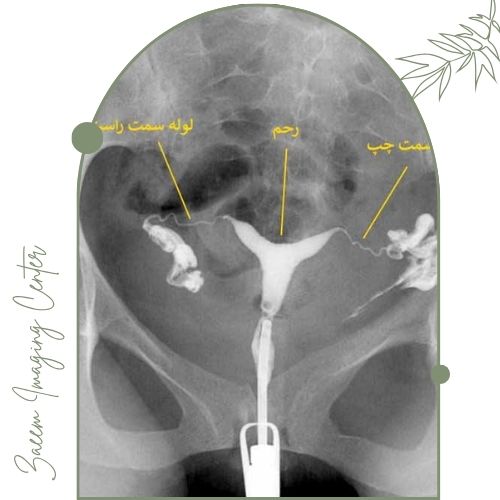

عکس رنگی رحم

در این مرکز ابزارهای تصویربرداری مدرن و استانداردهای بهروز جهانی مورد استفاده قرار میگیرند. دستگاههای نسل جدید با بهرهگیری از فناوری تصویربرداری تخصصی اطلاعات مورد نیاز را فقط در چند دقیقه جمعآوری کرده و همه اطلاعات در کنار تفسیر تخصصی تیم پزشکی در کوتاهترین زمان در اختیار شما قرار میگیرد تا گزارش نهایی کاملاً تخصصی و قابل استفاده توسط پزشکان جراح باشد. خدمات شامل موارد زیر است:عکس رنگی رحم (هیستروسالپنگوگرافی) برای ارزیابی باز بودن لولههای رحم و مشکلات ناباروری